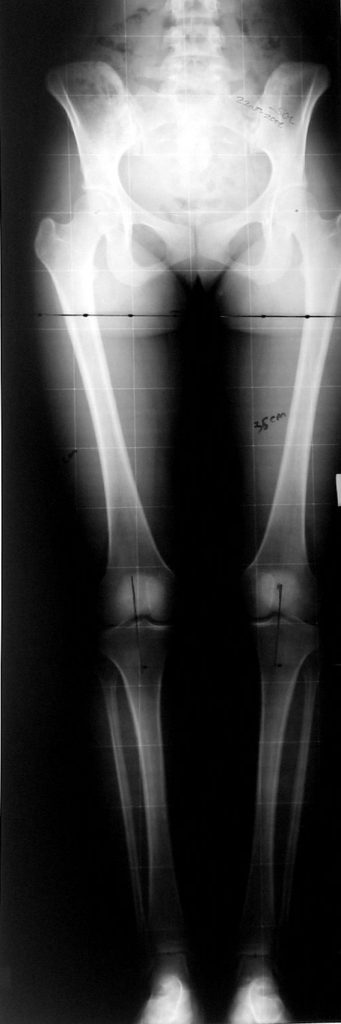

Lower limb length discrepancy is more than just a cosmetic problem; it leads to functional orthopedic problems. Orthopedic surgeons are very interested in the treatment of this pathological condition because imbalance at the frontal plane causes changes in walking pattern, and it also causes degenerative changes at the axial skeleton.

Today the most important properties that an extemity lengthening method shall possess are application time, ability to correct alignment (anatomic and mechanical axis of the extremity), number of total operations required, ability to protect the regenerated bone from refracture, minimum rate of pin tract site infection and possible complications, preservation of joint motion, healing time, comfortability in daily life and application cost.

In selected cases, we prefer to use a combination of a unilateral dynamic axial fixator and an interlocked intramedullary nail, in order to protect the length and alignment after the completion of the lengthening procedure. As a prerequisite for this technique, the narowest diameter of the medullary cavity shall be wider than 7 mm and the length of the nail segment distal to the osteotomy site shall be at least 8 cm. after the completion of the lengthening procedure.The intramedullary nail neutralizes shear and bending forces on femur during lengthening, shortens external fixation time, and protects newly formed bone against fractures. In our series, subtrochanteric osteotomy was performed in one case. No varus angulation occured despite the intramedullary nail.

Despite low sample size, our aim was to compare two groups with matching ethiology, age, location and amount of the deformity and other similar factors. We neglected simultaneous tibial lengthening and osteotomy site in this preliminary study. The sample size was not enough to conduct a prospective randomized trial. Although the results of the study did not produce statistically significant data, it is the first and only example in our country and conveys significant experience.